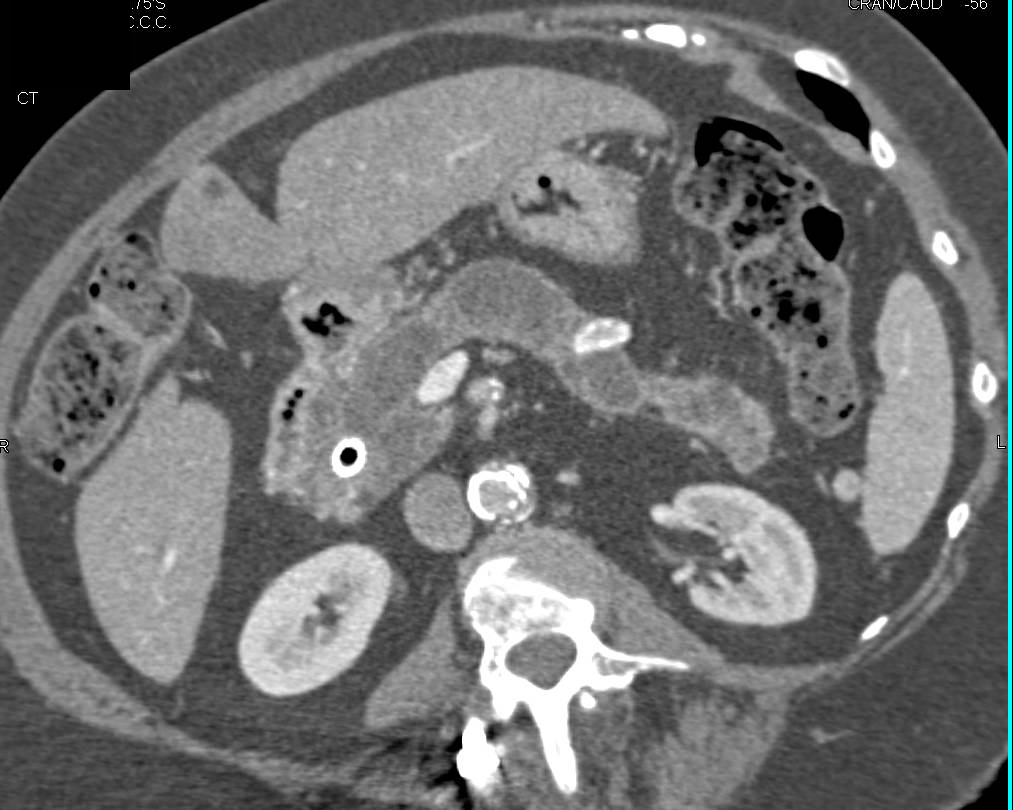

Cystic Metastases to the Pancreas Simulates a Pancreatic Adenocarcinoma